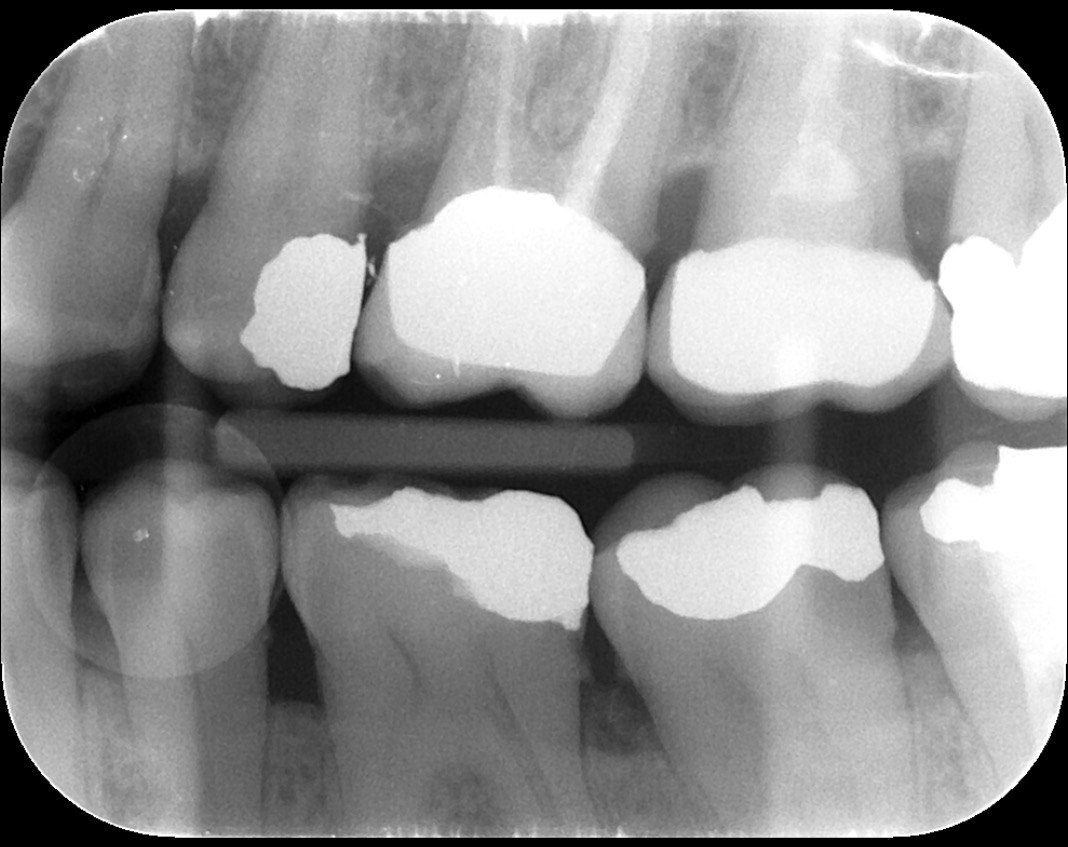

Question 1: What materials cannot be seen in the print of the X ray?

Question2: Which surface shows overhang?

Question 3: Which option is not evident on the print of the X ray?

Question 4: Which options cannot be seen in the print of the X ray?

Question 5: What options cannot be selected for tooth # 4.6?

Question 6: What options cannot be seen in the print of the X ray?

Question 7: What option cannot be identified on the print of the X ray?

Question 8: What condition can be seen in the X ray?

Question 9: Which option cannot be seen in the lower jaw?

Question 10: Which option can be selected for the following X ray?